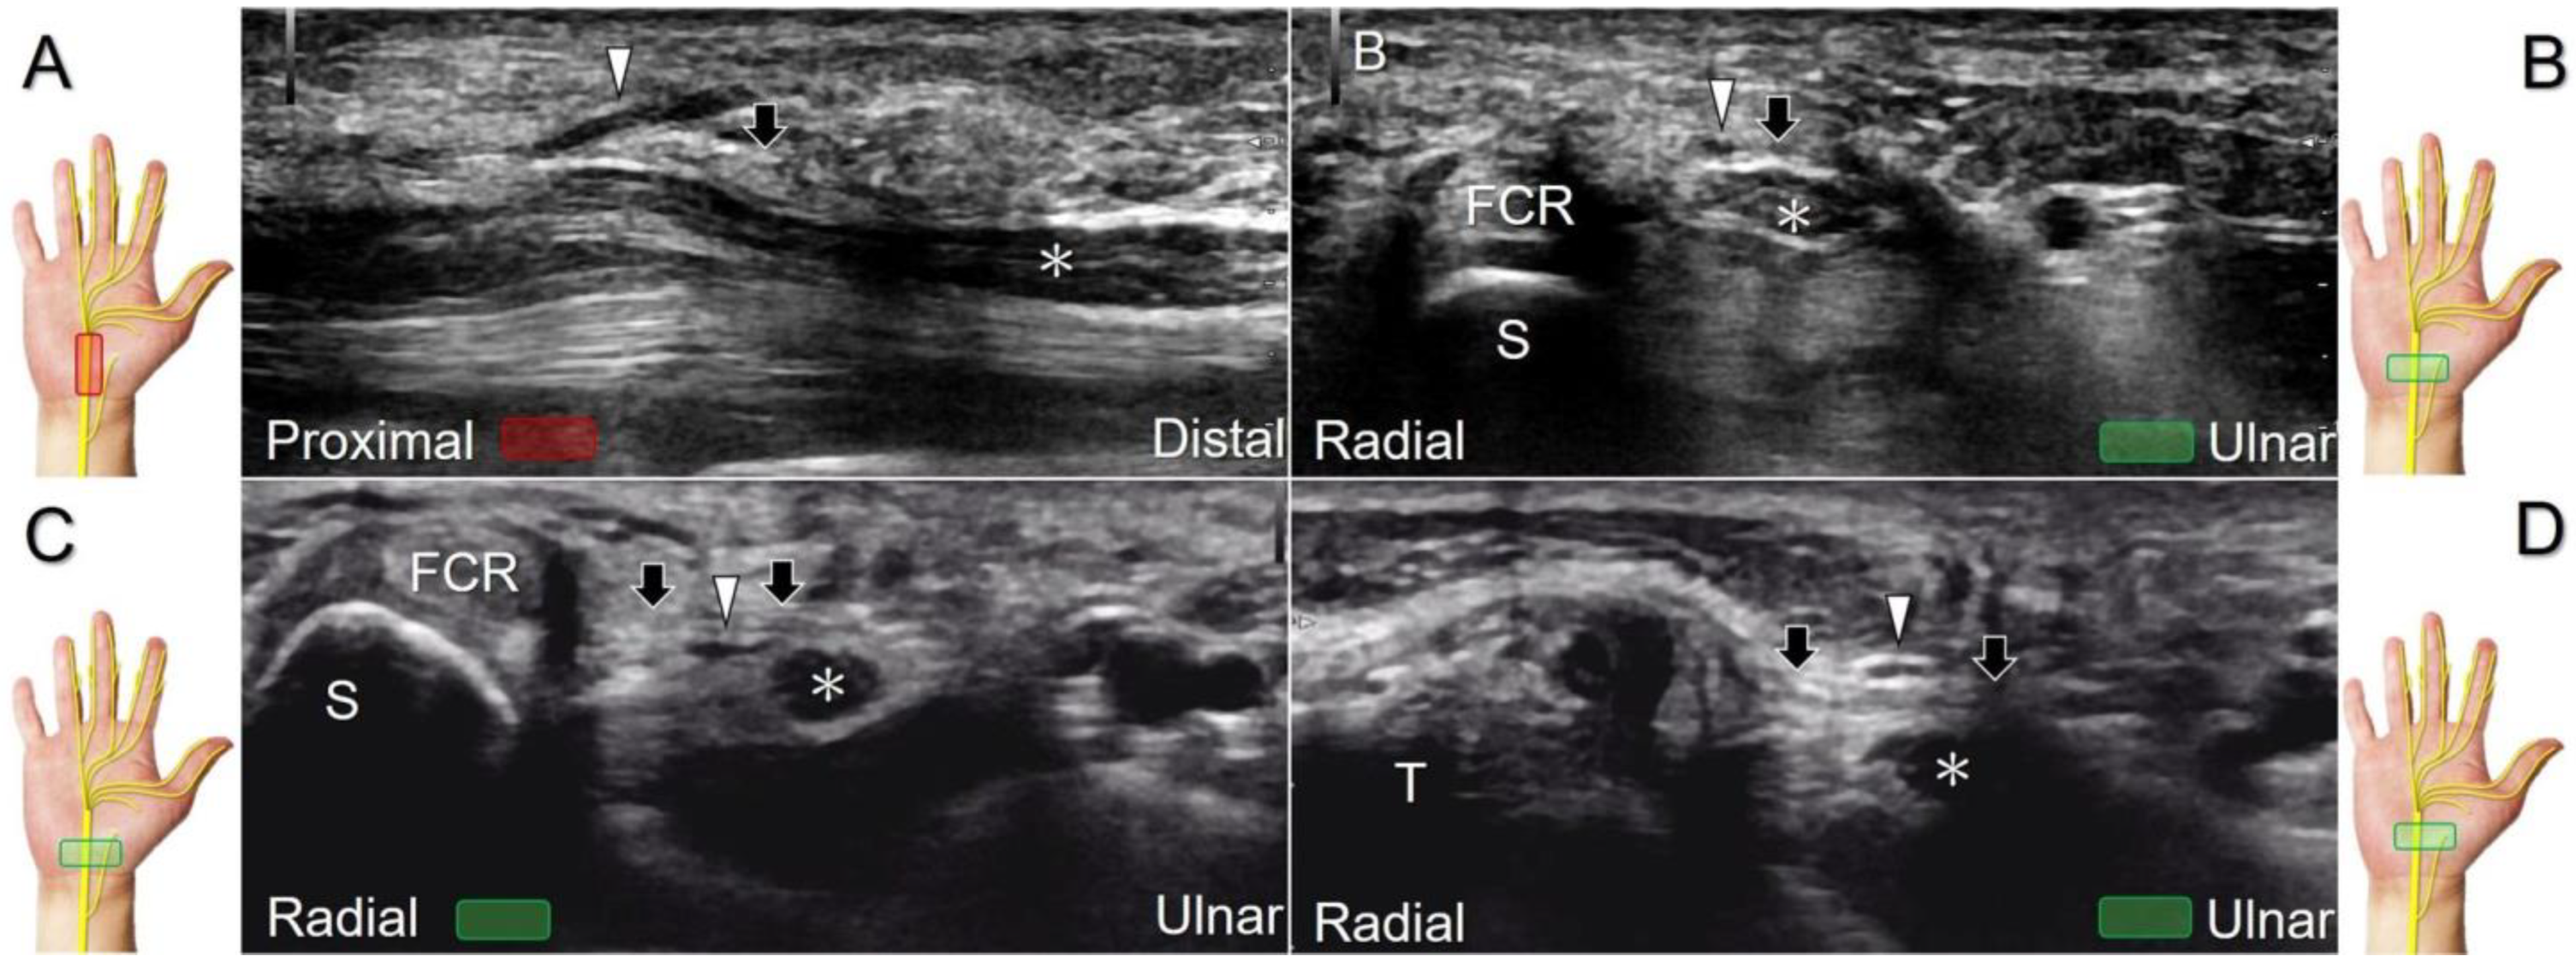

Figure 2. Sonographic/normal imaging of the median nerve from the inlet (A) to the outlet (B) of the carpal tunnel. Hypertrophy of the flexor retinaculum at both the inlet (C) and outlet (D) of the carpal tunnel. Asterisk: median nerve; small white arrowheads: normal flexor retinaculum; large arrowheads: hypertrophy of the flexor retinaculum. FCR: flexor carpi radialis; S: scaphoid; P: pisiform; T: trapezium; H: hook of the hamate.

The transducer can be placed in the axial plane on the distal one-third of the forearm with the forearm supinated. The median nerve travels between the flexor digitorum superficialis and flexor digitorum profundus muscles. It gradually runs superficially to enter the carpal tunnel. The carpal tunnel inlet is defined as the plane crossing the scaphoid and pisiform (Figure 2A), whereas the plane linking the trapezium and hook of the hamate serves as the carpal tunnel outlet (Figure 2B).

Clinical Implication

Carpal tunnel syndrome is the most common entrapment neuropathy whereby the median nerve is entrapped by various causes, like hypertrophy of the flexor retinaculum (Figure 2C,D) and compression from the accessory muscles, swollen tendons, ganglions, and bony fractures within the tunnel. Ultrasonographic changes encompass swelling proximal to the entrapment site (Figure 3A), flattening over the entrapment site (Figure 3B), intraneural hypervascularity (Figure 3C), and focal loss of the trimline pattern (Figure 3D).